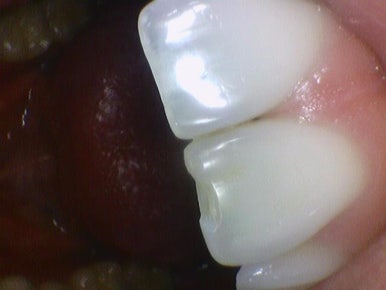

깨진 앞니 치료

살짝 깨진 앞니 치료